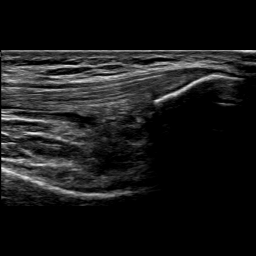

We focus on one of the three scans of the knee joint specified in HEAD-US protocol for the collection and diagnosis of joint recess distension in patients with hemophilia [7]: the SQR longitudinal scan. This scan is used to assess SQR distension and contains different characterizing elements (see Figure 1):

• The femur (blue box) usually appears as a light thick line, approximately horizontal, starting from the left side of the image and extending towards the right, often in the lower half of the image.

• The patella (red box) usually appears as a curved light line, positioned at the right border of the image, often in the top half and not entirely captured. The tendons (horizontal and parallel darker lines) can be seen on its left.

• The SQR (green box) often contains at least a small quantity of liquid and hence it is dark. In some cases, the joint recess membrane can be visible in grey. The joint recess is positioned between the femur and the patella. Its size and shape vary depending on many factors including whether it is distended or not, as explained below.

Figure 1b shows how the probe must be positioned during the acquisition of the SQR longitudinal scan. In the figure, the yellow box is the area that is captured by the US image shown in Figure 1a, while the green box is the SQR. To correctly acquire this type of image, the knee has to be bent at 30. The probe must be positioned right at the beginning of the patella and moved horizontally to identify the correct key features previously described.

Refer to caption

(a) Example of SQR longitudinal scan

(b) Probe positioning

Figure 1: Image acquisition